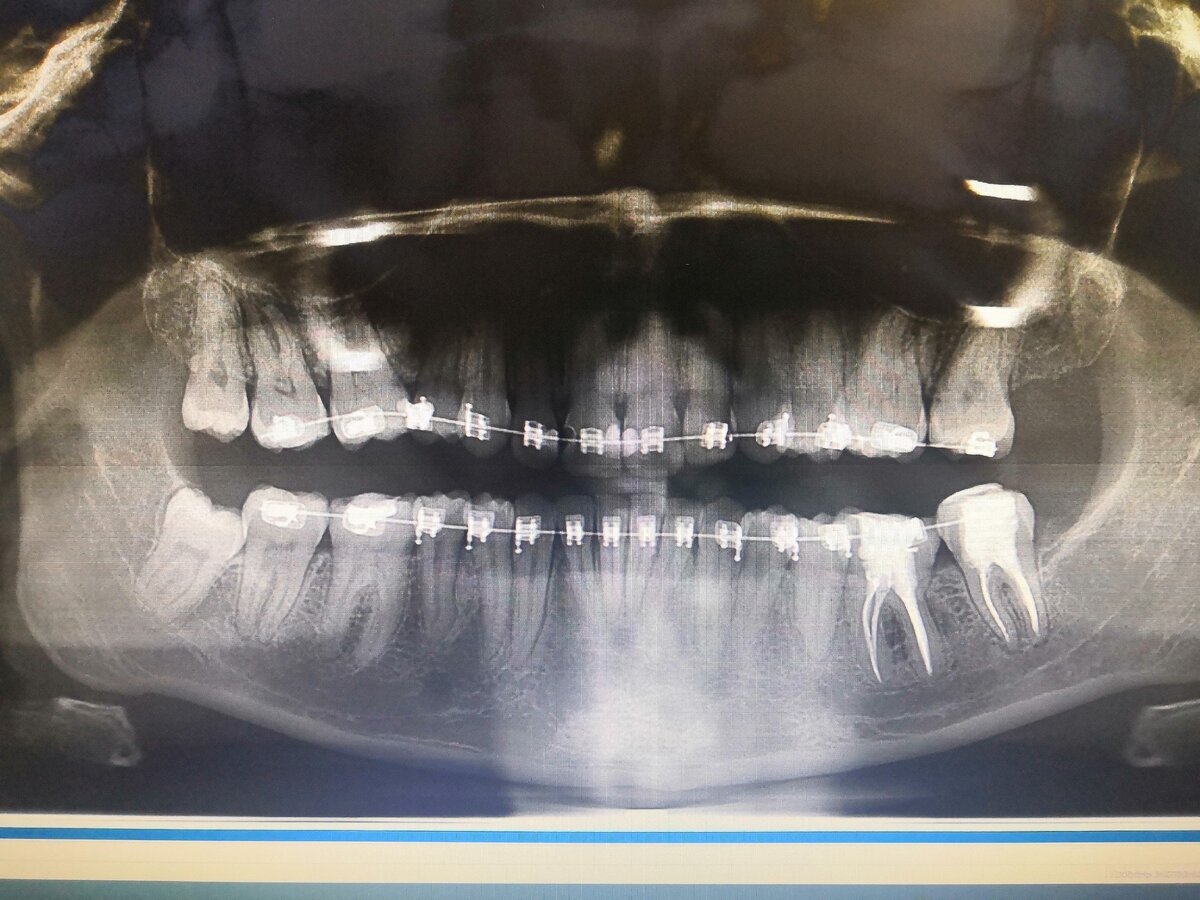

Но, я житель России Матушки и желание иметь красивую улыбку меня терзало с детства.Поэтому,спустя два года,после моего последнего визита к ортодонту,я собралась с духом и твердо решила довести это дело до конца. Скажу Вам,что до момента установки брекет системы,мне предстоял длительный период подготовки,поскольку необходима была справка от ЛОРа, ОПТГ снимок,вылечить весь кариес,сделать проф.гигиену,после этого ортодонт снимет слепки и только на следующем приеме Вам установят "железки" на зубы, и то,только на одну челюсть,на вторую челюсть можно будет поставить их только через несколько недель(В этой статье я не буду расписывать о том,какие бывают брекеты,какие лучше,хуже,кому интересно,спрашивайте в комментах,я отвечу).

Вечером,того же дня,как мне поставили брекеты,началась жуткая боль,зубы болели ужасно,я не могла ни есть ни говорить,малейшее прикосновение к зубам сопровождалось резкой болью.Так было каждый месяц,после визита к ортодонту и активации(это процедура,когда врач меняет дуги и лигатуры).Боль меня сопровождала первые пять дней после активации,а потом стихала.Со временем я привыкла к "железкам" во рту,ко второму месяцу я вовсе перестала их замечать и,тем более,стесняться.Зубы стали быстро становится на свои места,но срок лечения,тем не менее, длился два года.В течении этого срока мне необходимо было каждый месяц приходить на активацию.

На фото выше Вы видите мой результат ДО и ПОСЛЕ.Теперь любое фото сопровождалось улыбкой)))Ощущения передать невозможно,зубы перестали "ныть",мне предстояло учится смеяться " на все 32".